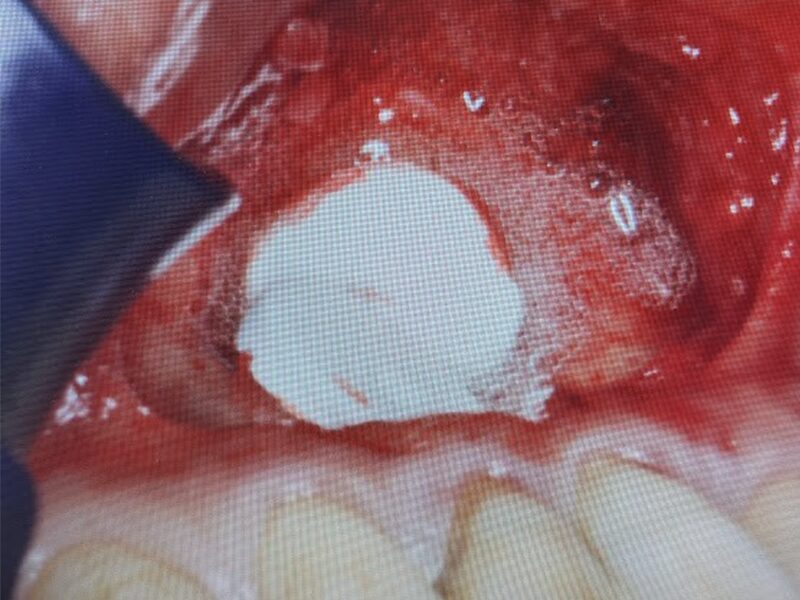

骨再生補填材を入れます。

タブレット状のボナーク(骨再生補填材)で封鎖いたします。